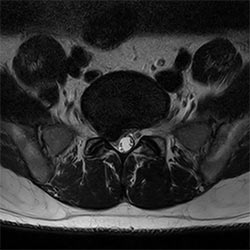

In a society where reimbursements are declining and chronic conditions lead to increased MR procedures and longer waiting times, there is ever increasing pressure on the radiology department. Today, further attempts to accelerate, compromise image quality or are limited to a narrow range of scans. Therefore, to meet the increased demand for productivity, a technology break-through in acceleration is still required. Leveraging our long standing leadership position in speed (i.e. SENSE), Philips brings compressed SENSE, a breakthrough in productivity.

Learn more about the main principles of Compressed SENSE and how it introduces a paradigm shift in productivity, how Compressed SENSE was designed around image quality, and how it advances productivity for clinical MR imaging.